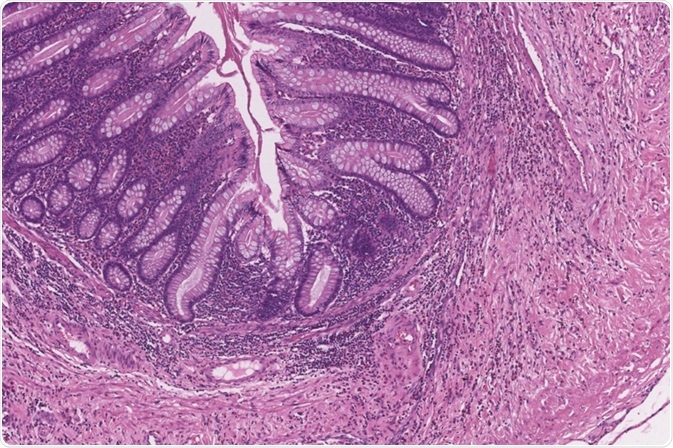

Subtotal Colectomy

Image Credit: Java Jar/Shutterstock.com